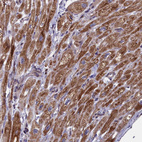

Immunohistochemical staining of human heart muscle shows moderate to strong granular cytoplasmic positivity in cardiomyocytes.